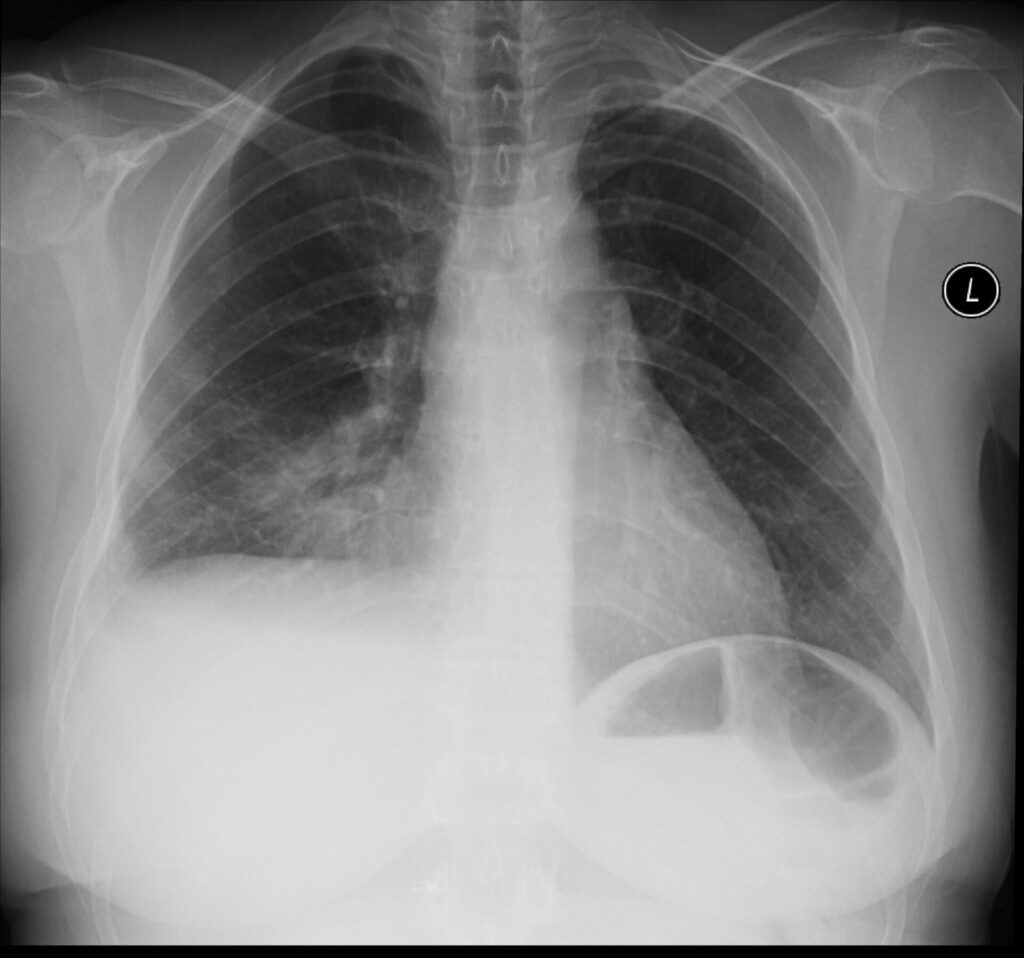

Konventionelle Radiologie heute

Die Bildgebung in der Medizin hat in den letzten Jahrzehnten rapide Fortschritte gemacht – von der klassischen Röntgenaufnahme über die […]